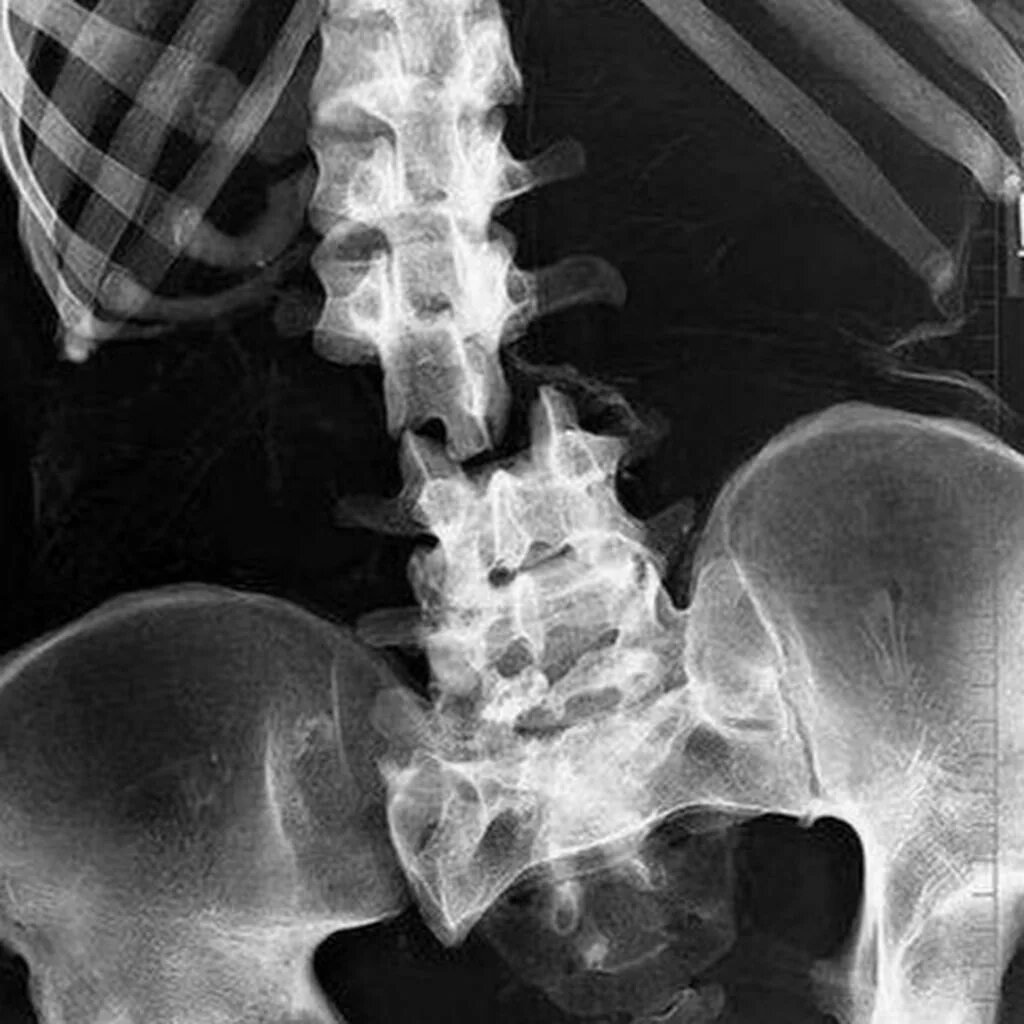

Задание   №  14 .

Продолжим?)  -  на   фото- рентгеновский   снимок ,   попробуйте   определить,

1. какие   части    тела    человека    на   снимке?

2. есть  ли   перелом?

Ответ  05.02.26    после  09.00   по   мскв  .

По ощущениям, нижняя часть тела . Будто тазовый пояс, перелом есть , шейка бедра со смещением . Возможно, еще и перелом компрессионный нижних поясничных позвонков .

Ответ  на   Задание   №  14 .

По ощущениям, нижняя часть тела . Будто тазовый пояс,   есть ,перелом  шейка бедра со смещением . Возможно, еще и перелом компрессионный нижних поясничных позвонков

Абсолютно   верно)🏅 перелом   позвонков,   поясничный  отдел.  Скорее   всего-  травма..

Скрытый текст

1. какие   части    тела    человека    на   снимке?  Основное-  нижняя    часть  Позвоночного   столба   и   кости  таза,   "  в   кадр "   частично  попали  ребра и бедренные   кость  с  одной   стороны

2. есть  ли   перелом? да,   есть   перелом   позвоночника.

рентген 2.jpg

Благодарю  за   участие   в   сложном  задании  ) Молодцы!)